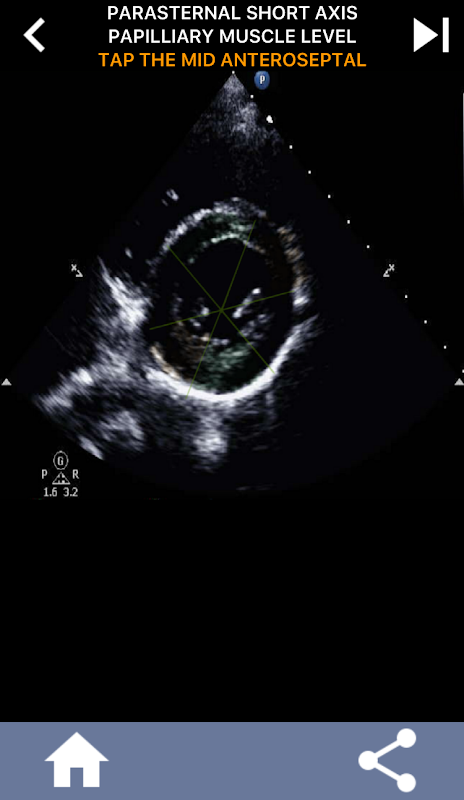

نهج مرئي قائم على الاختبار لتعلم قطاعات القلب AHA: تخطيط صدى القلب

يعد فهم قطاعات القلب من جمعية القلب الأمريكية (AHA) أمرًا في غاية الأهمية بالنسبة لأخصائي تخطيط الصدى القلبي للتواصل بشكل فعال مع طبيب القلب الذي يكتب التقرير. من خلال معرفة المناطق التشريحية المحددة والقطاعات المقابلة لها ، يمكن لأخصائي الموجات فوق الصوتية أن يصف بدقة أي تشوهات أو نتائج ونقلها ، مما يضمن التواصل الواضح والموجز بين كلا المهنيين.

يصبح هذا الفهم حاسمًا بشكل خاص عندما يسعى طبيب القلب إلى التأكد من الموقع الدقيق للمشكلة أو عندما يحدد الطبيب عند الطلب مشكلة داخل منطقة معينة ، مما يدفع أخصائي الموجات فوق الصوتية لعرض المقطع المقابل بدقة ، مثل الجدار الأوسط السفلي. وبالتالي ، فإن امتلاك فهم شامل لمقاطع القلب AHA هو مجموعة مهارات أساسية.

سيختبر هذا التطبيق معرفتك باستخدام صور صدى فعلية ، والتي أجدها غالبًا أفضل طريقة تدريس.